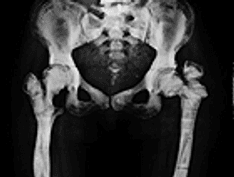

Surgical treatment of congenital coxa vara. Progression from preoperative radiographs at ages 2 and 5 years, with characteristic bony changes. Postoperative radiographs at ages 6 and 12 years, with early and late follow-up results.